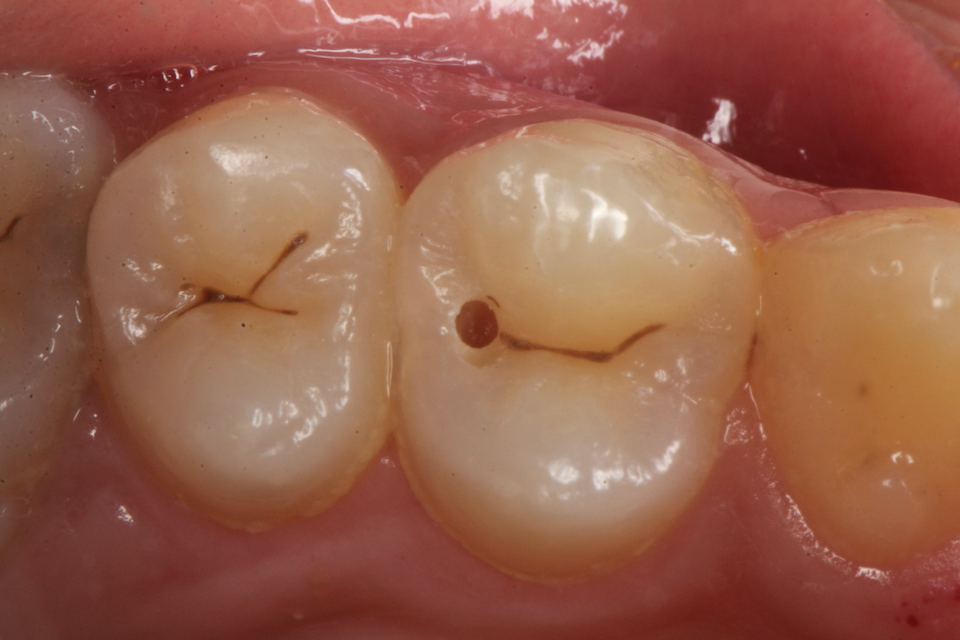

下顎7番の頬側歯茎部カリエスの原因 2025.06.04